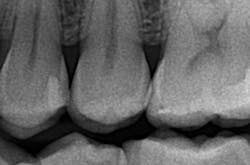

Although the radiographic appearance of these restorations is somewhat unfamiliar, they show long-term success (figures 4a–4b).

Figures 4a and 4b: Radiographic appearance and four-year follow-up of minimally invasive Class II tunnel cavity preparation on tooth 12D